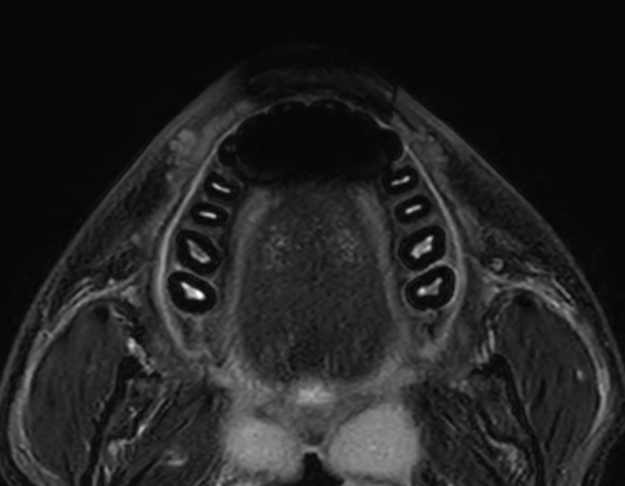

RM Lingua

Purtroppo le immagini dell’articolo non sono più disponibili, cerchero’ di ripristinarle appena possibile. Mi spiace per il disagio. QUESTIONARIO CLINICO Traumi? Qual’è il motivo specifico per cui viene eseguito l’esame? Interventi chirurgici alla lingua? Radioterapia? Biopsie? Dolori? Intermittenti? PREPARAZIONE DEL PAZIENTE: Il paziente deve essere a digiuno da 4 ore (in relazione all’eventuale iniezione di…